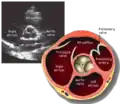

This view is obtained in the same window as the parasternal long, but with the probe rotated 90°. In this view, the aortic valve is seen in cross-section with the right ventricular inflow & outflow tracts visible with the tricuspid valve as well. Pulmonary valve is not visible in this view. Both the right and left atria are visible.

- Aortic valve in short-axis

- Aortic valve area by planimetry

- Color doppler of all four valves

- Spectral doppler of tricuspid and pulmonary valves